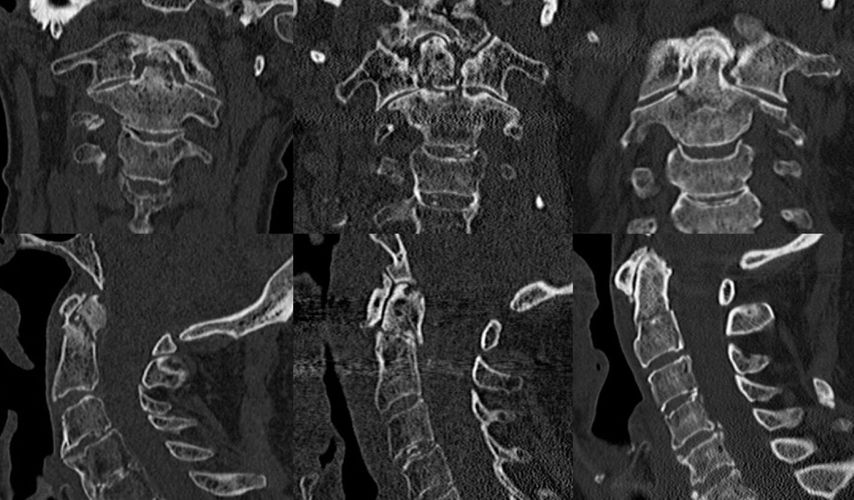

Densfrakturen können nach Anderson und D’Alonzo in 3 Typen eingeteilt werden (Abb. 1):14

Abb. 1: CT-Bilder a.p. (obere Reihe) und seitlich (untere Reihe) von Typ-I- (links), Typ-II- (Mitte) und Typ-III-Frakturen (rechts)

Typ-II-Frakturen können nach Grauer et al. weiter unterteilt werden in Typ IIa (quer verlaufend), Typ IIb (von anterior superior nach posterior inferior verlaufend) und Typ IIc (von anterior inferior nach posterior superior verlaufend).15